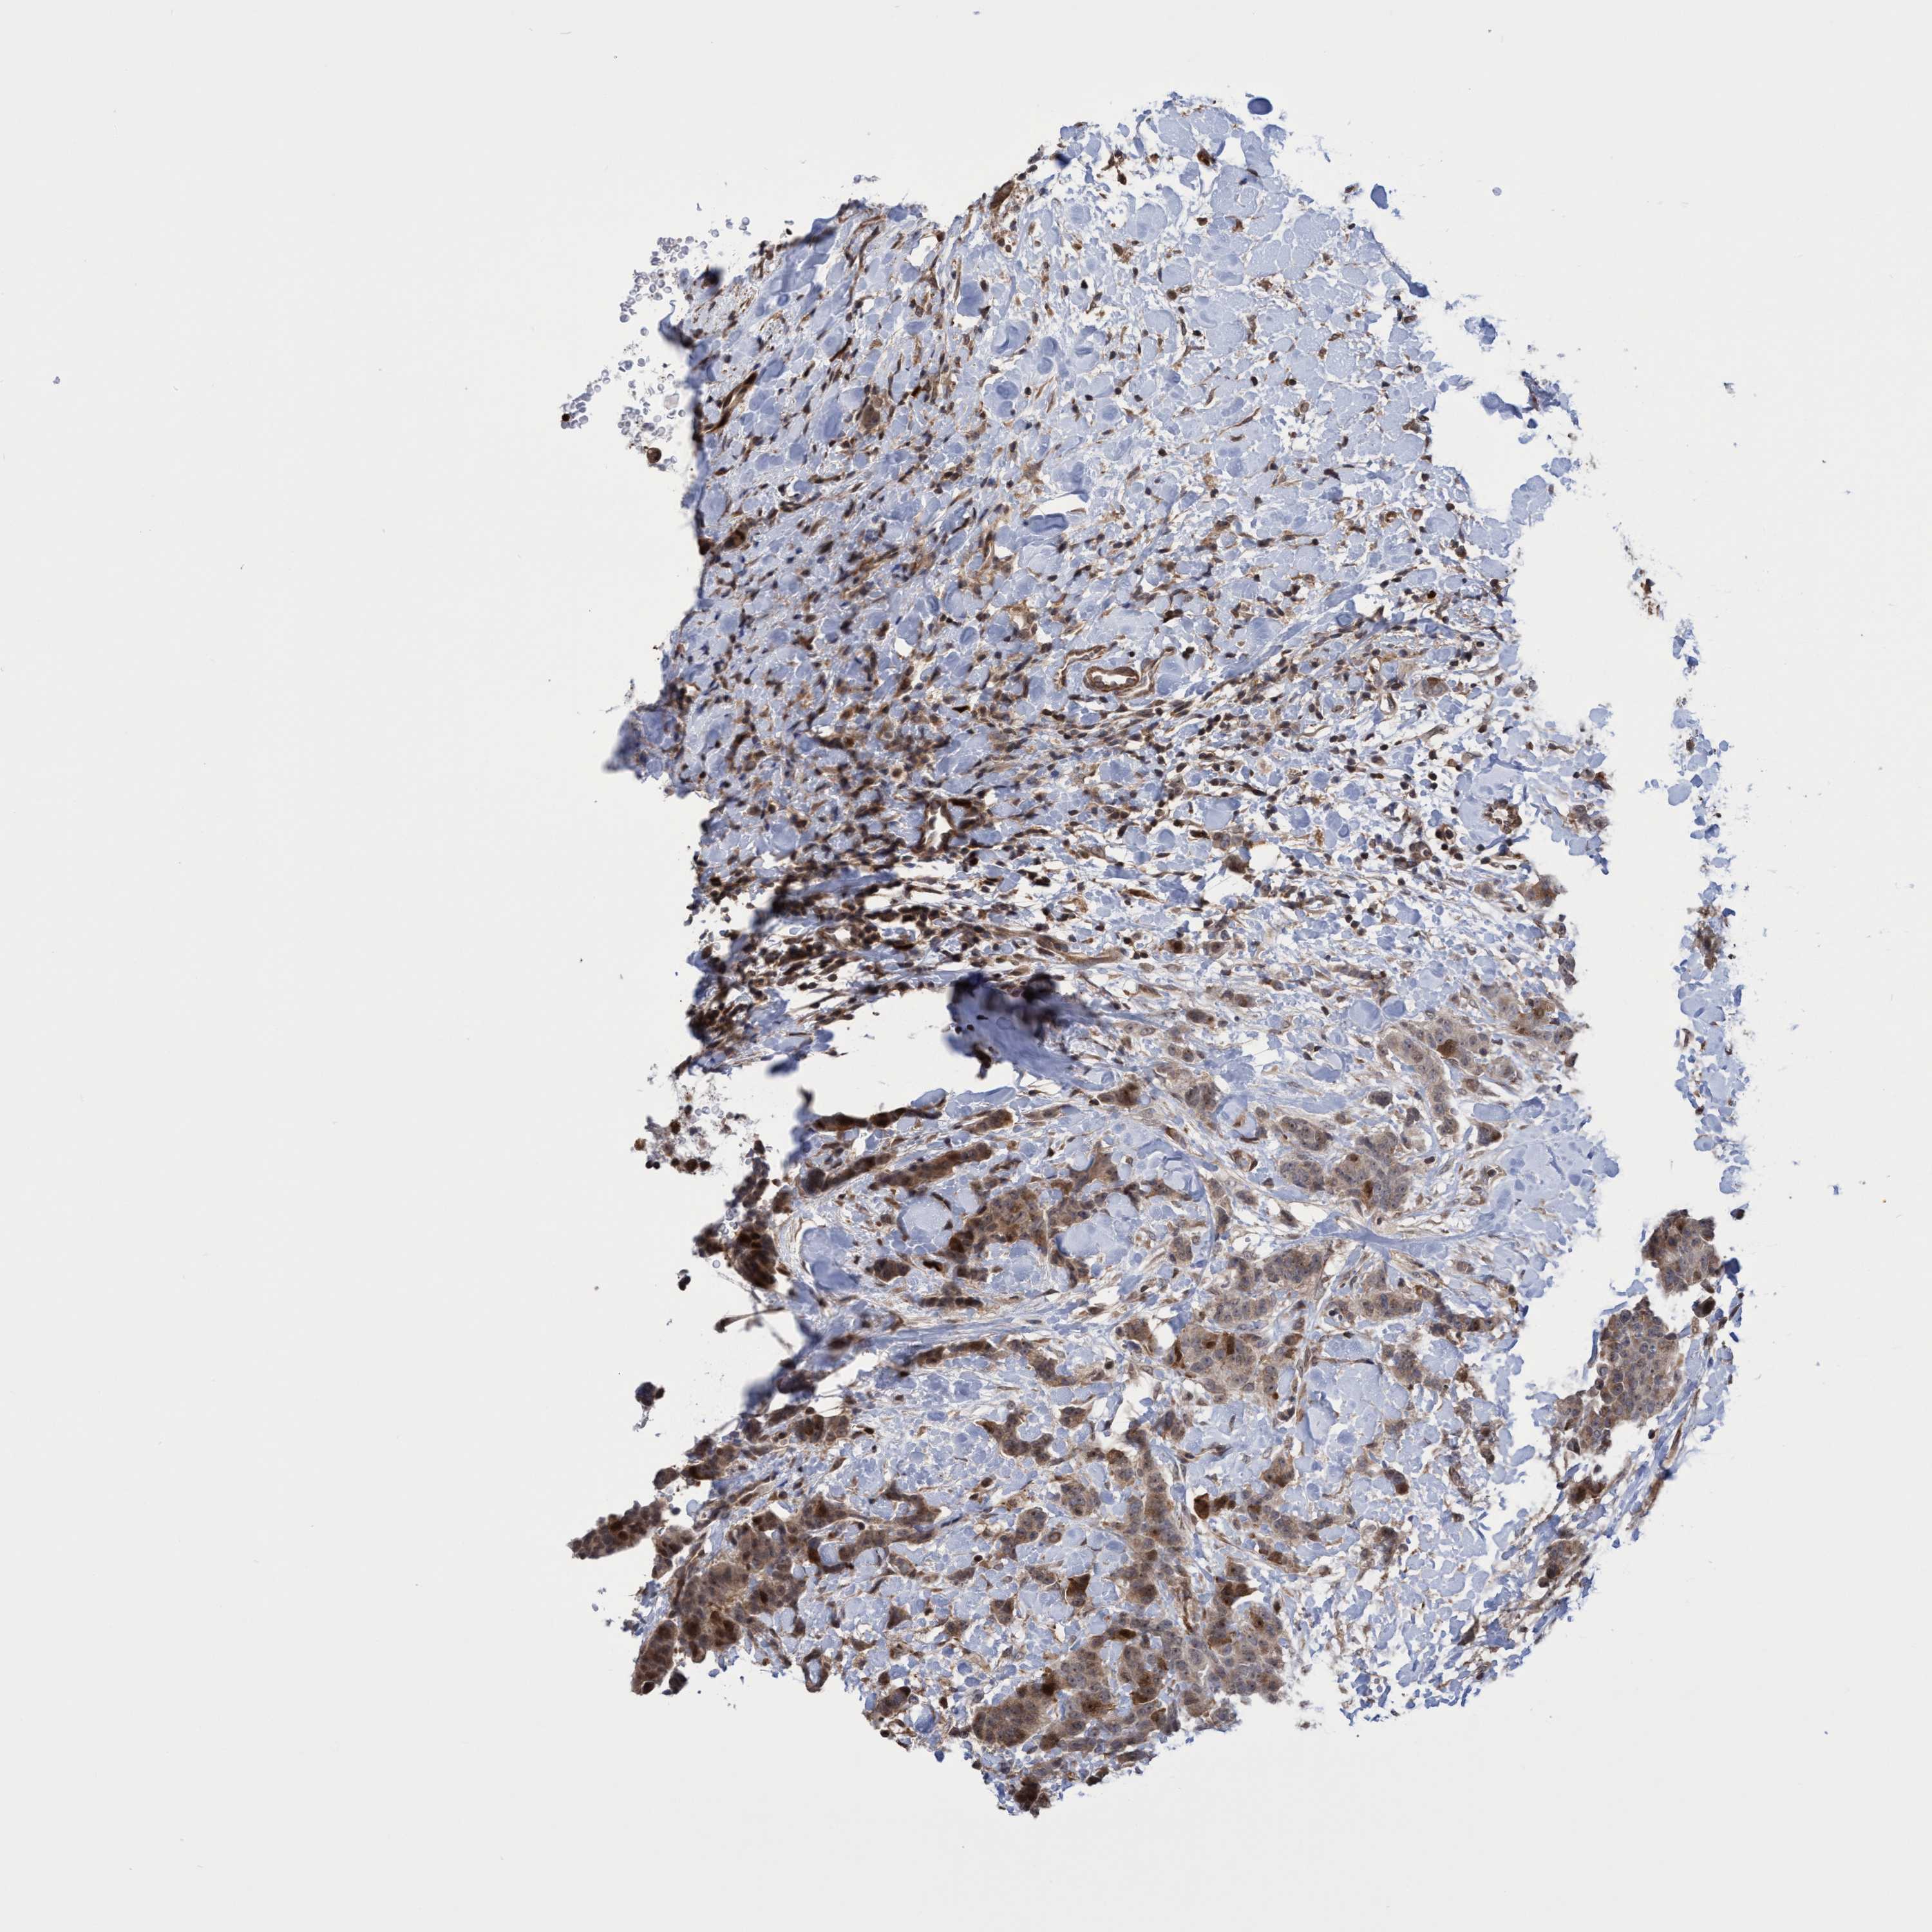

CANCER BREAST CANCER Show tissue menu

BRCA TCGA BRCA VALIDATION PROTEIN EXPRESSION

Breast cancer

Human cancer

SLBP is not prognostic in Breast Invasive Carcinoma (TCGA)